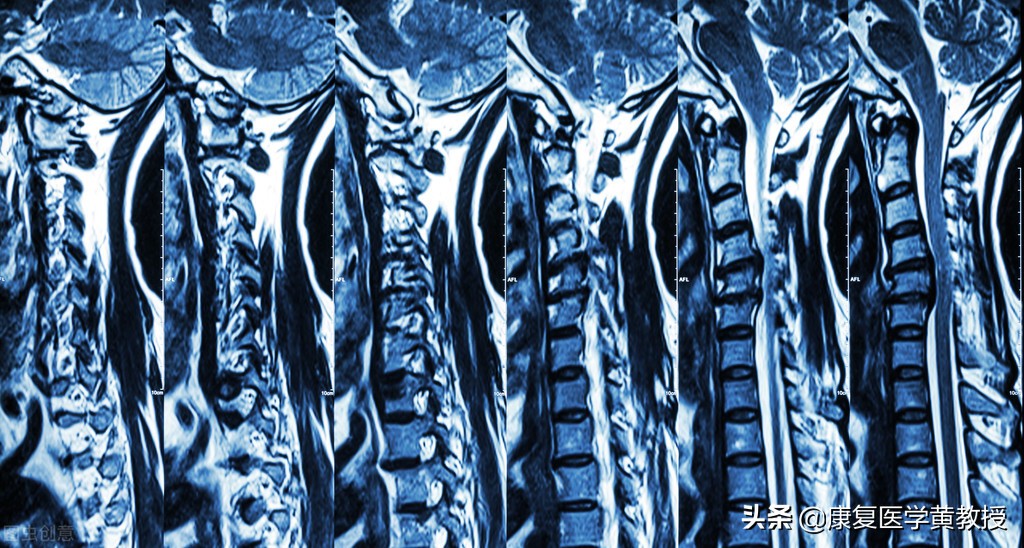

我们会前往医院寻求帮助的最重要的原因就是不舒服的症状,可能是肩颈僵硬,可能是头晕影响生活,于是开始在医院里寻求相关科室治病,选择有骨科,中医科,针灸推拿科,神经内科,疼痛科,最不会考虑的就是康復科(原因稍后再聊),医生开始尽责地利用设备及各种手段,想尽办法得出一个疾病的名称,来安抚患者的心情,让患者知道自己真的生病了, 于是检查报告中出现了颈椎生理曲度变直,颈3-4,颈4-5,颈5-6椎间盘膨出,突出,韧带出现钙化现象,骨质增生,椎管狭窄,因此患者就会问怎麽治?多久会好? 黄教授在此告诉你,这个病不会好,如果你觉得没有症状就是好,那么吃药打针或者中医方面的方法都是可以解决症状的问题,可是你要认清楚一个事实,你的生活依然在继续,你的年纪一直在老化,身体的机能一直在减弱,那么如果透过现代医疗手段,是可以将症状减轻或消除了,但颈椎病不会好,相关的症状会在未来的某一天继续地伤害你,也或许像感冒一样,频繁出现折磨影响我们的生活.